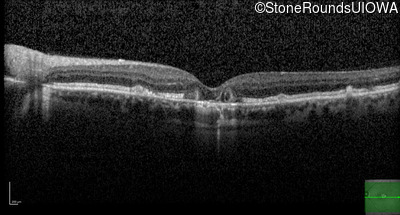

Optical Coherence Tomography - Right - 20/25

Exemplar / OCT Stack